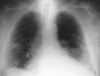

Рентгенологические находки при пневмонии

Пневмония в правой средней доле с исчезновением определяющегося контура анатомической структуры на рентгенограмме

Такая рентгенография грудной клетки показывает наличие инфильтрата, который маскирует правую границу сердца (признак "утраты контура"). Признак "утраты контура" указывает на размытое изображение 2 структур, которые имеют похожую рентгенконтрастность; к правой границе сердца примыкает правая средняя доля легкого, таким образом, в этой доле диагностируется наличие инфильтрата и пневмонии.